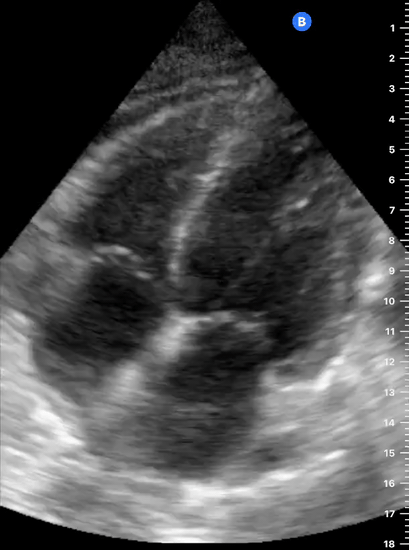

THE VIEWS

The A4C view provides an accurate chamber size comparison. However, achieving a proper A4C view (avoiding foreshortening or ballooning, and visualising the four chambers with a vertically oriented interventricular septum) can be a challenging exercise of image acquisition. Additionally, the PSAX view at the level of the papillary muscles shows both LV and RV side by side and is useful to assess function and size. When RV pressure is high, the septum will be pushed and flattened towards the LV, resulting in the characteristic “D-shaped” LV or “D sign”.